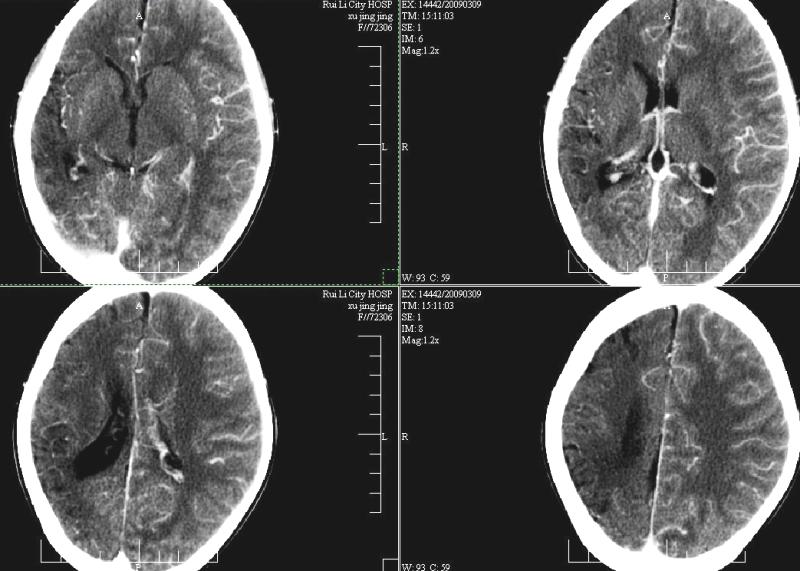

支持楼主!右侧强化明显较左侧低.可能血管引起的吧.

支持楼主!右侧强化明显较左侧低.可能由血管发育不良引起的吧.

支持大脑发育不全----右侧大脑中动脉较对侧细小。建议cta 或mra 检查